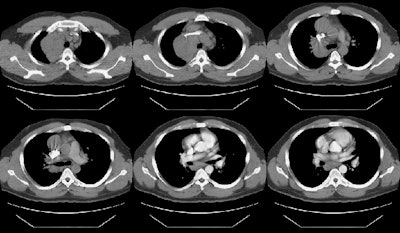

The film below was from 1997. The right paratracheal mass has enlarged markedly in comparison to the patients old film. This finding was felt to be atypical for sarcoid and a CT was performed.

The CT scan demonstrated a large anterior mediastinal/right paratracheal mass which severely compressed the superior vena cava, coupled with mediastinal and subcarinal adenopathy. Mediastinoscopy was performed and the patient was discovered to have Hodgkins lymphoma.